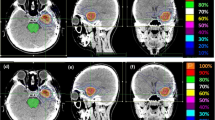

Distributions of the decision objectives of individual target volumes (Fig. 1) as well as individual patients (Fig. 2) were directly compared between the SRS plans and CyberKnife plans.